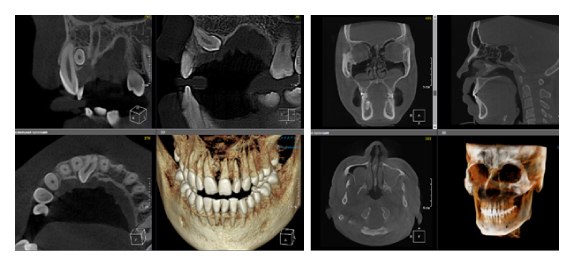

Когда мы отправляем пациента на проведение рентгенологического исследования, то подвергаем его определенному риску. Именно это нужно осознавать, так как в радиологии нет минимально безопасной дозы, поэтому любое назначение должно быть обоснованным. В связи с этим поле обзора является достаточно принципиальным параметром. Если вы врач-терапевт, занимающийся эндодонтией или ортопед, который решил оценить состояние зубов перед протезированием, то вы должны понимать, что проведение исследования с полем обзора 10x10 см будет гораздо информативнее нежели большие снимки (18x16 см и выше). В первую очередь это связано с размером вокселя, о нём я напишу чуть ниже, а второе это то, что вам придется увеличивать изображение по каждому корневому каналу, и от этого вы будете терять в качестве снимка (рис. 1). И ситуация наоборот, если вы ортодонт, то чтобы использовать весь диагностический потенциал, а также возможность загрузить данные для расчёта 3D цефалометрии, то вам нужны снимки, захватывающие весь лицевой отдел черепа. Таким образом, дентальный томограф должен обладать возможностью проведения исследований с разным FOV, обеспечивая нужды всех специалистов. Если ваша клиника базируется на терапевтическом, хирургическом и ортопедическом приёме, то на мой взгляд, можно рассмотреть дентальные томографы с полем обзора 10x10 см или 16x10 см. Последний больше актуален для тех, кто работает с ВНЧС, так как антропометрически в 16 см даже у брахицефалов сустав должен попадать.  Если в клинике есть ортодонтическое направление, функциональная стоматология, ЛОР-практика или ЧЛХ, то, безусловно, вышепредставленные снимки не будут отражать всех данных, которые необходимы для диагностики и планирования лечения. Здесь лучше рассмотреть конусно-лучевые компьютерные томографы с зоной сканирования 18x16 или 20x20 см. Особо стоит отметить понятие «сшивки». Есть дентальные томографы, которые делают один цельный снимок размерами, которые описаны выше, а есть аппараты, которым нужно провести две экспозиции и сшить изображения вместе, чтобы получился необходимый объём исследования. Как правило, вторые томографы чуть дешевле, но всё зависит от того, насколько вам нужна максимальная точность исследования. Если при сшивке челюсти и зубы, как правило, совмещаются практически идеально, то на уровне позвоночного столба происходит наслоение тканей и от него уже не избавиться (рис. 2). Второй отрицательный момент – это износ оборудования, логично, что он будет быстрее, так что экономия средств — это ещё спорный вопрос.

Рис. 1. Представлены два исследования (10x10 см и 20x20 см). На обоих изображениях хорошо видна канально-корневая система зубов, но, если масштабировать второе исследование, то качество неминуемо снизится, как и диагностическая эндодонтическая эффективность.